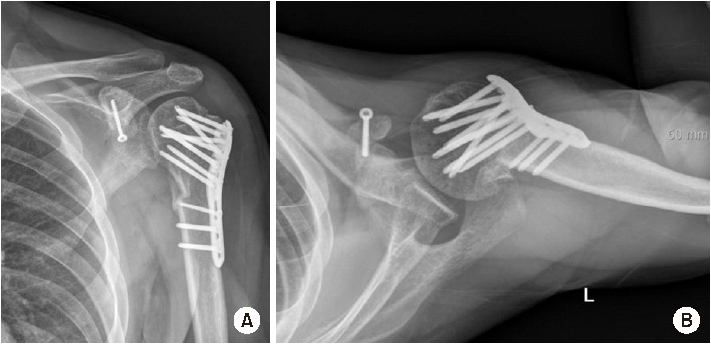

Shoulder Quadruple Dislocation Fracture: Fracture of Glenoid Rim, Coracoid Process, Greater Tuberosity, Surgical Neck of Humerus Associated with Anterior Shoulder Dislocation: A Case Report

Shoulder joint dislocation has the most common incidence rate compare compared to other joints. It is reported that shoulder Shoulder dislocation couldmay be associated with glenoid rim, greater tuberosity of humerus and coracoid process fracture. There were have only been 2 cases of anterior shoulder dislocation simultaneously combined with simultaneous glenoid rim, coracoid process, and humerus greater tuberosity fracture worldwide and no report reports in Korea. We present a case of quadruple fracture (glenoid rim, coracoid process, greater tuberosity, surgical neck of humerus) associated with anterior shoulder dislocation and treated successfully by open reduction. In addition, with we provide the injury mechanism, diagnosis, treatment procedure and discussion.